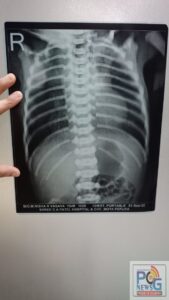

સિમલી ગામની ૨૩ વર્ષની નિશા વસાવાએ પી.પી.પી. મોડલ હેઠળ ચાલતા સી.એચ.સી.માં તેના બીજા બાળકને જન્મ આપ્યો હતો. ગુરુવારે સવારે ૫.૩૯ વાગ્યે ૩૧ અઠવાડિયે જન્મેલ માદા બાળકનું વજન ૧.૪૪૦ કિગ્રા છે. જોકે ડોકટરોએ ટ્રેચીઓ એસોફેજલ ફિસ્ટુલા નામની વિકૃતિ સાથે બાળક જન્મેલ છે તેમ જણાવ્યું. આ રોગમાં સામાન્ય રીતે ખોરાકની પાઈપ પેટ સાથે જોડાયેલી નથી હોતી જેના કારણે શિશુમાં સ્વાસ્થ્ય સંબંધી ગૂંચવણો ઊભી થાય છે.

રાષ્ટ્રીય બાલ સ્વાસ્થ્ય કાર્યક્રમ યોજનાને કારણે આ આદિવાસી પરિવાર હવે વિનામૂલ્યે સર્જરી કરાવી રહ્યું છે. બાળક અત્યારે નિયોનેટલ આઈ.સી.યુ.માં નિરીક્ષણ હેઠળ છે અને ડૉક્ટરના અભિપ્રાય બાદ તેને ટર્સિયરી કેન્દ્ર, એસ.એસ.જી. અને પછી અમદાવાદમાં સર્જરી માટે ખસેડવામાં આવશે. આ યોજના સારવાર, સર્જરી, પરિવહનના બધાજ ખર્ચને આવરી લે છે. સરકાર દ્વારા ચલાવવામાં આવતી રાષ્ટ્રીય બાલ સ્વાસ્થ્ય કાર્યક્રમ જેવી કેટકેટલી યોજનાઓ સમાજના જરૂરિયાતમંદ લોકો માટે આશીર્વાદરૂપ બની છે અને નવજીવન આપવામાં સફળ થઈ રહી છે.